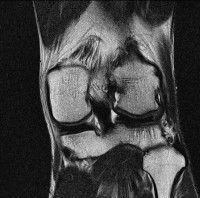

무릎 mri 간단히 봐주실 수 있으시나요 ㅠㅠ

안녕하세요 8년전 십자인대 수술하고 최근 무리한 운동에 무릎 불편감이 생겨서

mri 찍었습니다.

진단결과는 첫 찍은 병원에서 활액막염 이라는 진단을 받았습니다. 혹시 봐주실 수 있으실까요?

올라온 MRI가 단편적이라서 정확한 진단에 어려움이 있지만 십자인대에는 큰 이상이 있지는 않은것 같으며, 무릎관절내 물이 있는 것으로 보아 활액막염의 진단이 맞을 것 같습니다.

하지만 단편적인 영상이기 때문에 촬영병원에서 정확한 판독지 등을 받으시는 것이 좋겠습니다.